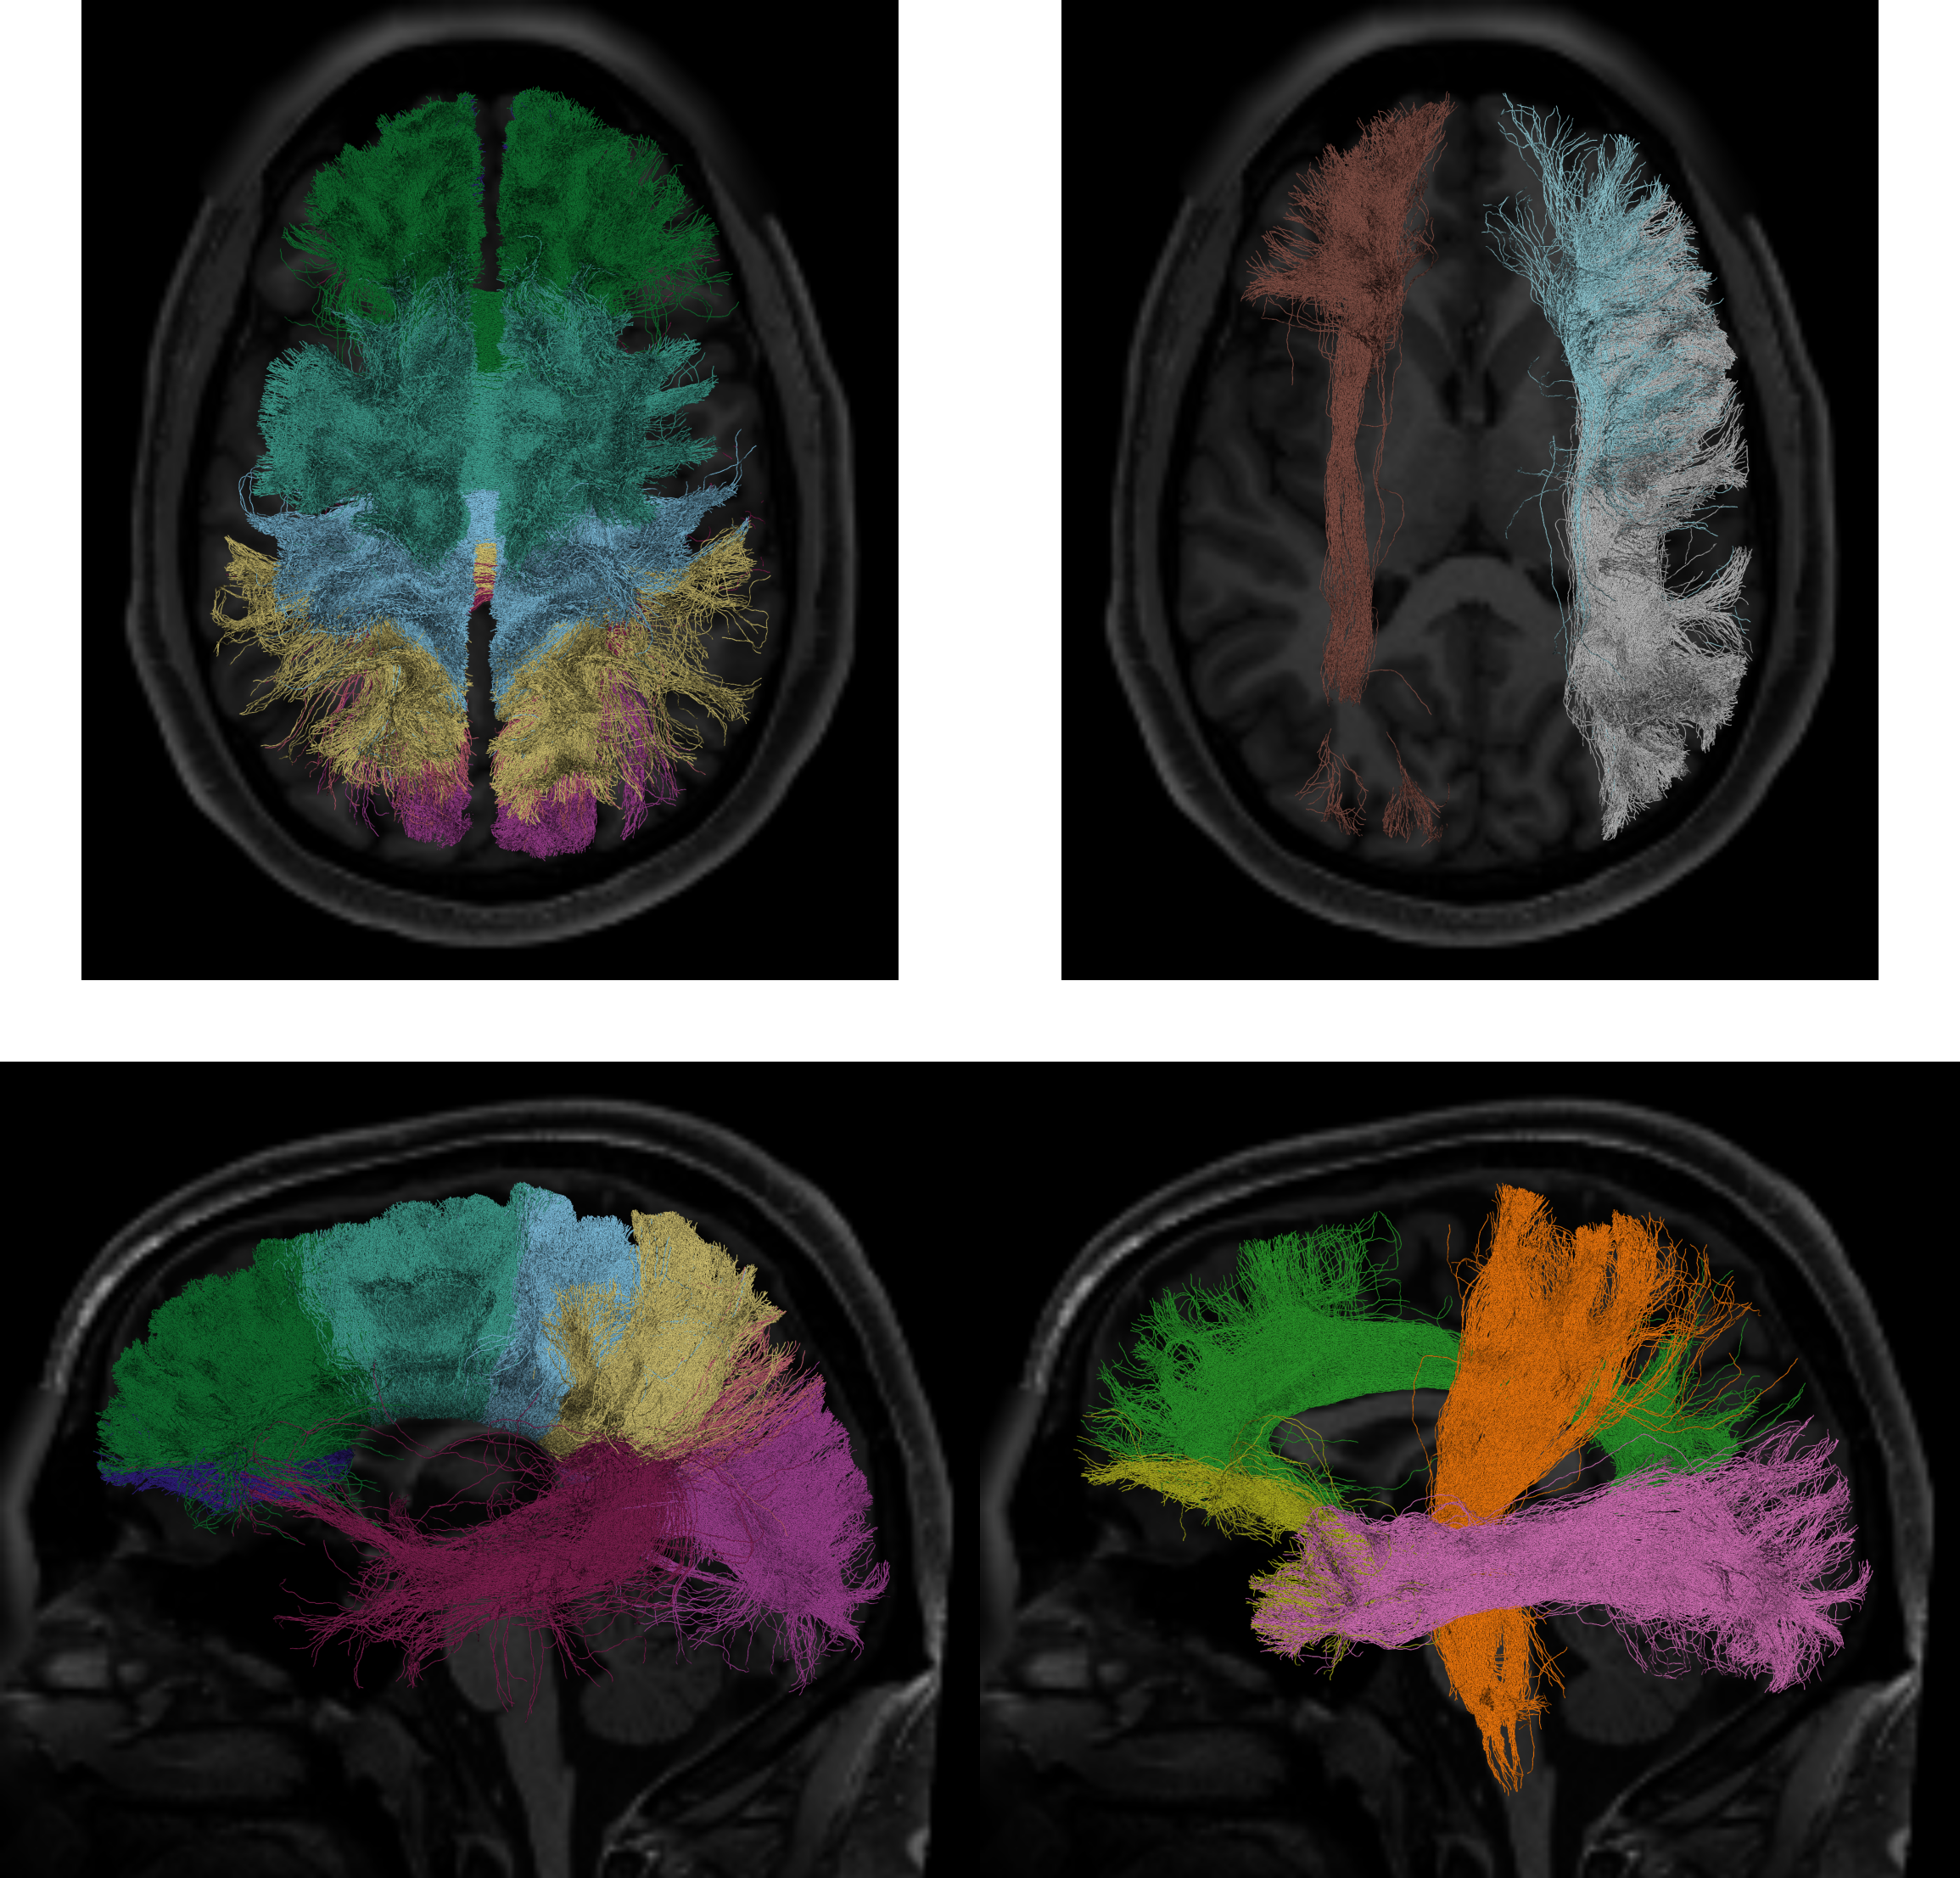

Basser (1994), Basser and Pierpaoli (1996)